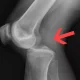

2. تصویربرداری با اشعه ایکس (X-ray): این تصویربرداری برای تایید دررفتگی زانو و بررسی شکستگی های احتمالی استخوان ها انجام می شود.

دررفتگی زانو یک آسیب بسیار جدی و اورژانسی است که در آن، استخوان های اصلی تشکیل دهنده مفصل زانو، یعنی استخوان ران (فمور) و درشت نی (تیبیا)، از هم ترازی و تماس طبیعی خود خارج می شوند. این آسیب شدت بسیار بیشتری نسبت به دررفتگی کشکک زانو دارد و نیازمند توجه فوری پزشکی است. به دلیل شدت بالای این عارضه، اغلب رباط های اصلی زانو دچار پارگی می شوند و احتمال آسیب به عروق خونی و اعصاب اطراف زانو نیز وجود دارد.

• تغییر شکل واضح زانو: زانو ظاهری کج و بدشکل پیدا می کند و مشخص است که استخوان ها در جای طبیعی خود قرار ندارند.